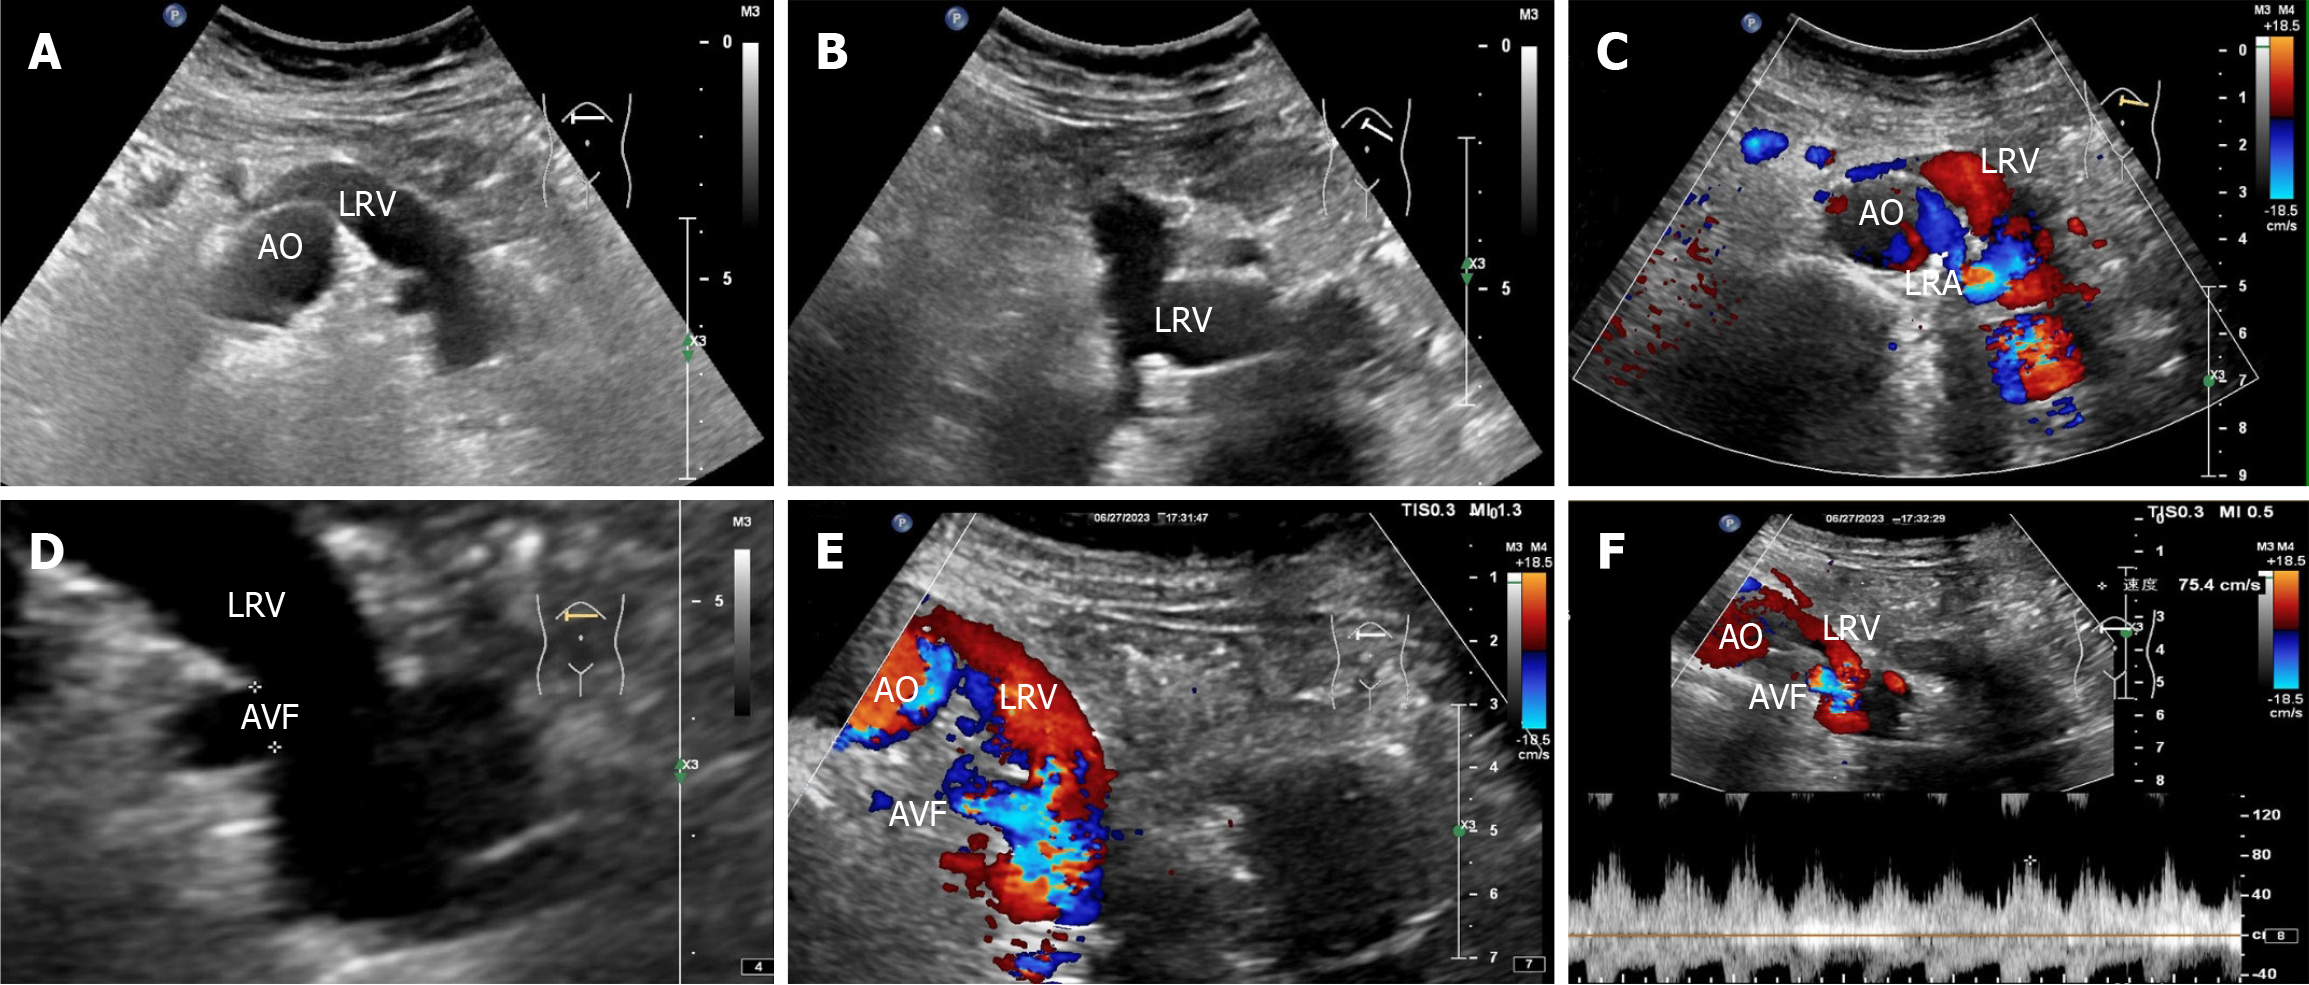

Renal ultrasonography revealed the possible presence of left RAVF in the kidney. To confirm the existence of RAVF outside the kidney, renal vascular ultrasonography was performed. 2D images revealed that the left renal vein was widened and uneven in thickness, with an internal diameter of 1.8 cm at the widest point (Figure 3A and B). CDFI re

When the RAVF is relatively small, there is no obvious manifestation on 2D ultrasound images. However, when the fistula is large, arterialization of the affected veins can cause the renal veins to become locally tortuous and dilated on 2D sonograms. The intrarenal veins appear spongy and show localized anechoic areas. In addition, the location and size of the fistula can be observed in 2D images. RAVF color doppler ultrasound reveals abnormal blood flow signals with high speed and turbulence in tortuous and dilated blood vessels. RAVF spectral doppler of blood flow has the characteristics of high speed, low resistance, burrs, and no empty window. This is because the arterial blood flow is shunted through the fistula and directly into the vein, which results in arterialization of venous blood flow.

An arterial-like flow spectrum is detected in the draining vein, which is a characteristic manifestation of ultrasound in diagnosing RAVF[10]. In this case, the patient’s 2D ultrasound images, color doppler, and spectral doppler ultrasound features were consistent with the ultrasound manifestations of RAVF, which supported the diagnosis of left RAVF. However, ultrasound revealed only one more obvious fistula on the outside of one kidney, without revealing the exact size of the fistula within the intrarenal pedunculated vascular mass. Notably, this patient had not only RAVF but also renal cysts in the left kidney. When the 2D ultrasound examination revealed several anechoic areas within or around the kidney, it was impossible to consider it a simple renal cyst based on conventional thinking. In such cases, color doppler flow should be activated. When blood flow signals are found in anechoic areas, spectral doppler should be used to observe the blood flow spectral characteristics to distinguish it from renal cysts. Color doppler ultrasound can easily distinguish RAVF from renal cysts. For anechoic lesions near the renal hilum in the central region of the kidney, especially small asymptomatic lesions, ultrasound may present a risk of missed diagnosis. Second, for patients with hematuria, in addition to considering common stones and tumors, ultrasound physicians should also consider renal vascular abnormalities as one of the rare causes of hematuria. In particular, when 2D sonography shows cystic lesions in the kidney, CDFI should be initiated to identify vascular abnormalities. The hematuria in this patient was caused by left RAVF, not by a left renal cyst.